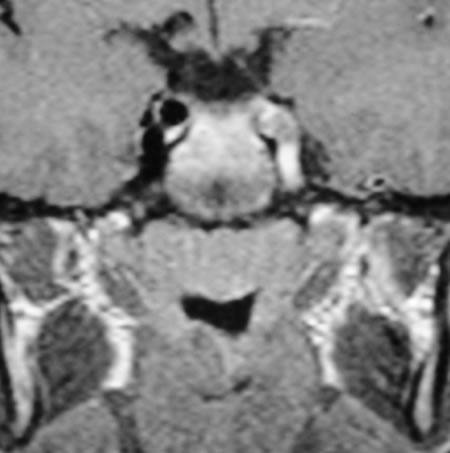

La ripetizione della TAC (Fig. 1) dopo alcuni giorni ha messo in evidenza alcune aree ipodense a sx, a livello parietale e temporo-mandibolare, che non presentano enhancement dopo mezzo di contrasto, dato che esclude un tumore o un ascesso. Finalmente esegue angio-RMN (Fig. 2) che mostra una occlusione della carotide interna in un quadro suggestivo di dissezione della carotide interna. A quel punto viene rivalutata la storia e ripete l'eco-doppler dei vasi del collo (Fig. 3 e Fig. 4) che mostra un ostruzione della carotide interna di sinistra ad 1 cm dalla biforcazione, senza alterazioni a destra. Il recupero del bambino è stato quasi completo.

Eco-doppler della carotide sinistra: ostruzione ad 1cm dalla biforcazione